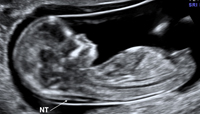

Criteria for Nuchal Translucency (NT) Measurement

1. Fetal CRL between 38-84mm

2. Margins of NT edges are clear

a. Clear image

b. Angle of insonation is perpendicular to

NT space

c. Clear NT lines

3. Fetus in Mid Sagittal plane

a. Midsagital view of fetal spine seen in

cervical & thoracic region

b. Tip of nose seen in fetal profile

c. Third & fourth ventricle seen in CNS

d. Should not see ribs, stomach or heart

4. Fetus occupies majority of image

a. Image predominately filled by fetal head

neck and thorax

b. The fetus should occupy >50% of image

5. Fetal head in neutral position

a. Amniotic fluid seen between chin and chest

b. Angle <90 degrees

6. Fetus observed away from amnion

7. Measurements

a. Use the + calipers

b. Place crosshairs on the inner edge, but not

in the clear space

c. Measurement is perpendicular to long axis

of the fetus

d. Measure at widest space

e. Use largest of 3 technically correct

measurements